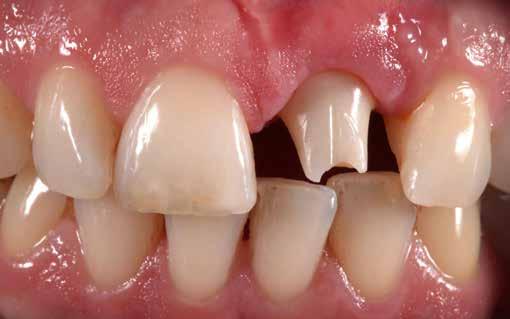

A felső frontfogak állapota elhanyagolt, a parodontális struktúrák részben erősen károsodottak, VMK korona az 12 zónában, az ínyszél szürke, fekete approximális háromszögek… vörös-fehér esztétikáról nem is beszélhetünk (1. kép). Így jelentkezett a hölgypáciens a Weston Dental Specialists Group rendelőben. Elvárásai magasak voltak. A defektusok kezelését, a gingiva lefutásának korrigálását kívánta. Gyorsan világossá vált, hogy a megoldást csak a négy frontfog teljes kerámiakoronával való ellátása jelentheti. A jelen eset bemutatja, hogy az IPS e.max ZirCAD Prime segítségével hogyan lehet tiszta, tetszetős és esztétikus mosolyt létrehozni.

1. kép: Kiindulási helyzet.